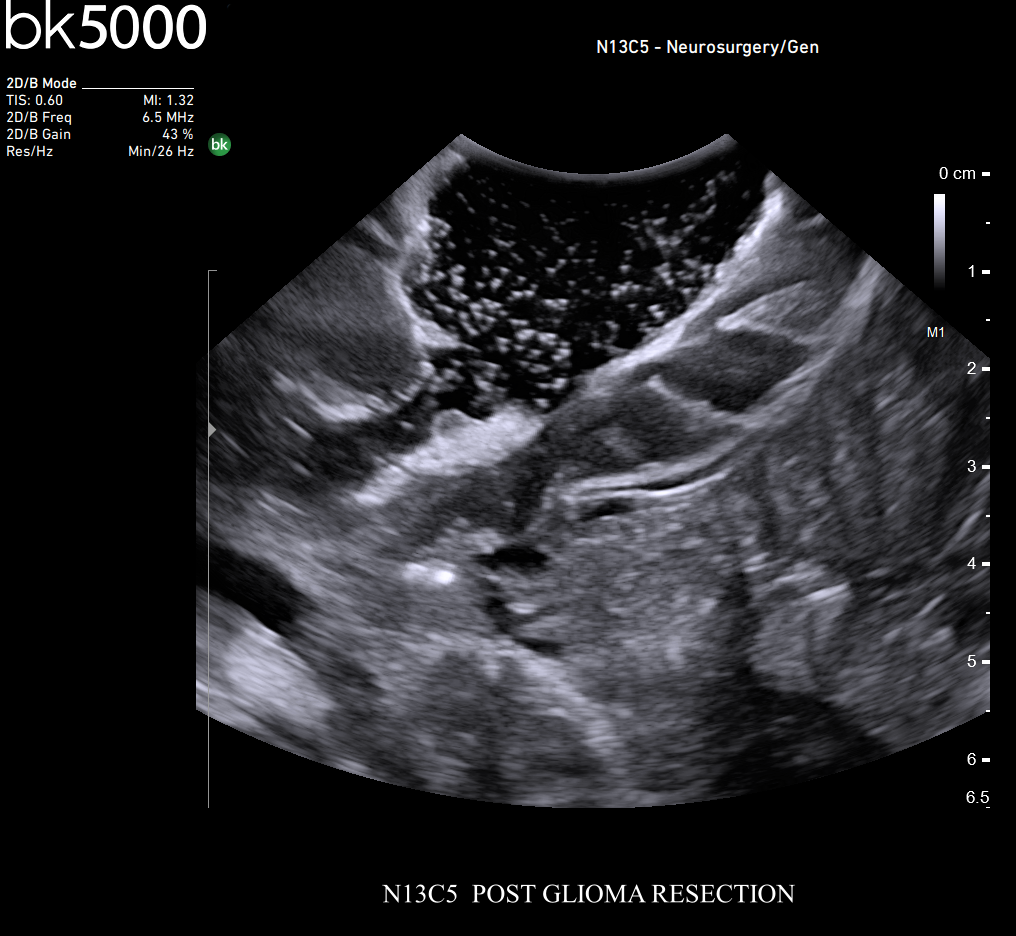

Premium Ultrasound Imaging in Neurosurgical Procedures

Ultrasound can improve neurosurgical procedures by helping you navigate and identify lesions and anatomical structures in real-time. This is particularly important as the data obtained from a preoperative CT or MRI scan can be outdated at the time of surgery. The bk5000 neurosurgical system provides the highest quality images that allow you to clearly see the margins of a lesion and to determine the best course of action. Using advanced graphics processing technology, this powerful system provides immediate, auto-optimized images that allow you to see the information you need, faster.

The specialized, high-resolution, sterilizable neurosurgery transducers enable you to obtain detailed images of the brain and spinal cord. They have a convenient Smart™ button that lets you activate the transducer, then freeze, store or print the images at the press of a button. Disposable, easy-to-use needle guides assist with targeting lesions.